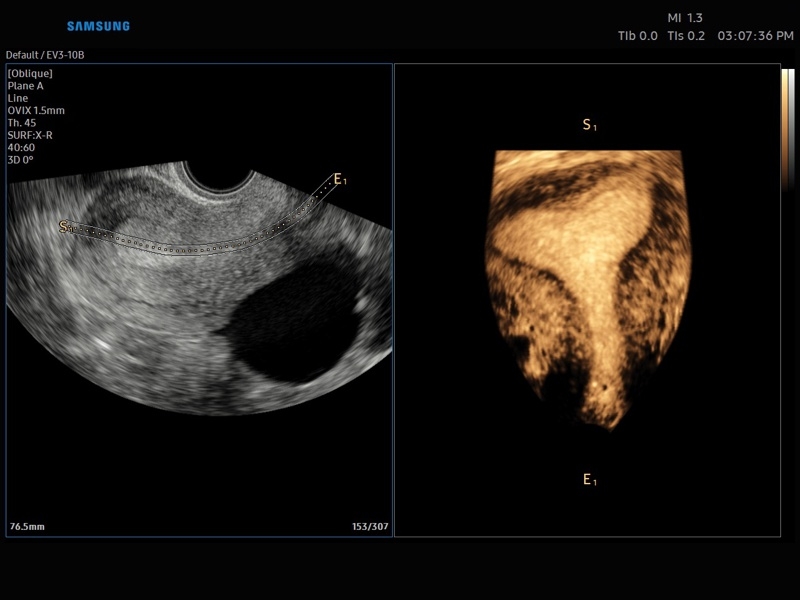

• Акушерство и гинекология

• OVIX(Oblique View eXtended) - получение фрагмента трехмерного изображения (в виде нескольких полупрозрачных сканов, последовательно наложенных один на другой) в направлении произвольного косого среза трехмерного объекта исследования.

• МодульCrystal Vue- программа реконструкции прозрачного 3D УЗИ, которое получается при одновременном усилении внутренних и наружных структур. Применяется для визуальной оценки состояния плода и матки, помогает лучше идентифицировать мягкие ткани и кости.

• Модуль Crystal Vue Flow- программа реконструкции прозрачного 3D УЗИ, которое получается при одновременном усилении внутренних и наружных структур. Применяется для визуальной оценки состояния плода и матки, помогает лучше идентифицировать мягкие ткани и кости. Так же визуализирует объемный кровоток.